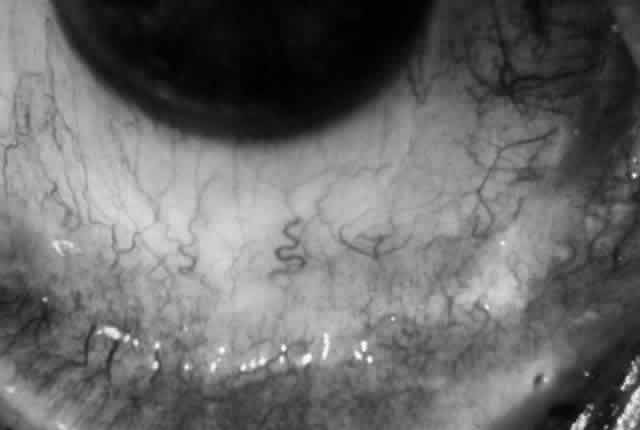

Clinically, the ocular disease in cicatricial pemphigoid (OCP) may present unilaterally in the form of a chronic, recurrent catarrhal conjunctivitis, but it eventually becomes bilateral. Subepithelial fibrosis is characteristic of stage 1 of OCP (Fig. 7). Stage 2 shows fornix foreshortening (Fig. 8), and symblepharon formation is the hallmark of stage 3 (Fig. 9). Stage 4, end-stage disease, is characterized by ankyloblepharon and surface keratinization (Fig. 10). Obstruction of the lacrimal ductules and meibomian gland ducts eventually produces an unstable tear film and progressive sicca syndrome, but it is to be emphasized that OCP is not a dry-eye syndrome until late in the disease course.20 Trichiasis and entropion occur because of the subepithelial fibrosis, with eventual keratopathy, corneal neovascularization, and corneal ulceration and scarring.20

Fig. 8. Stage 2 cicatricial pemphigoid, with fornix foreshortening and subepithelial fibrosis without frank symblepharon formation.